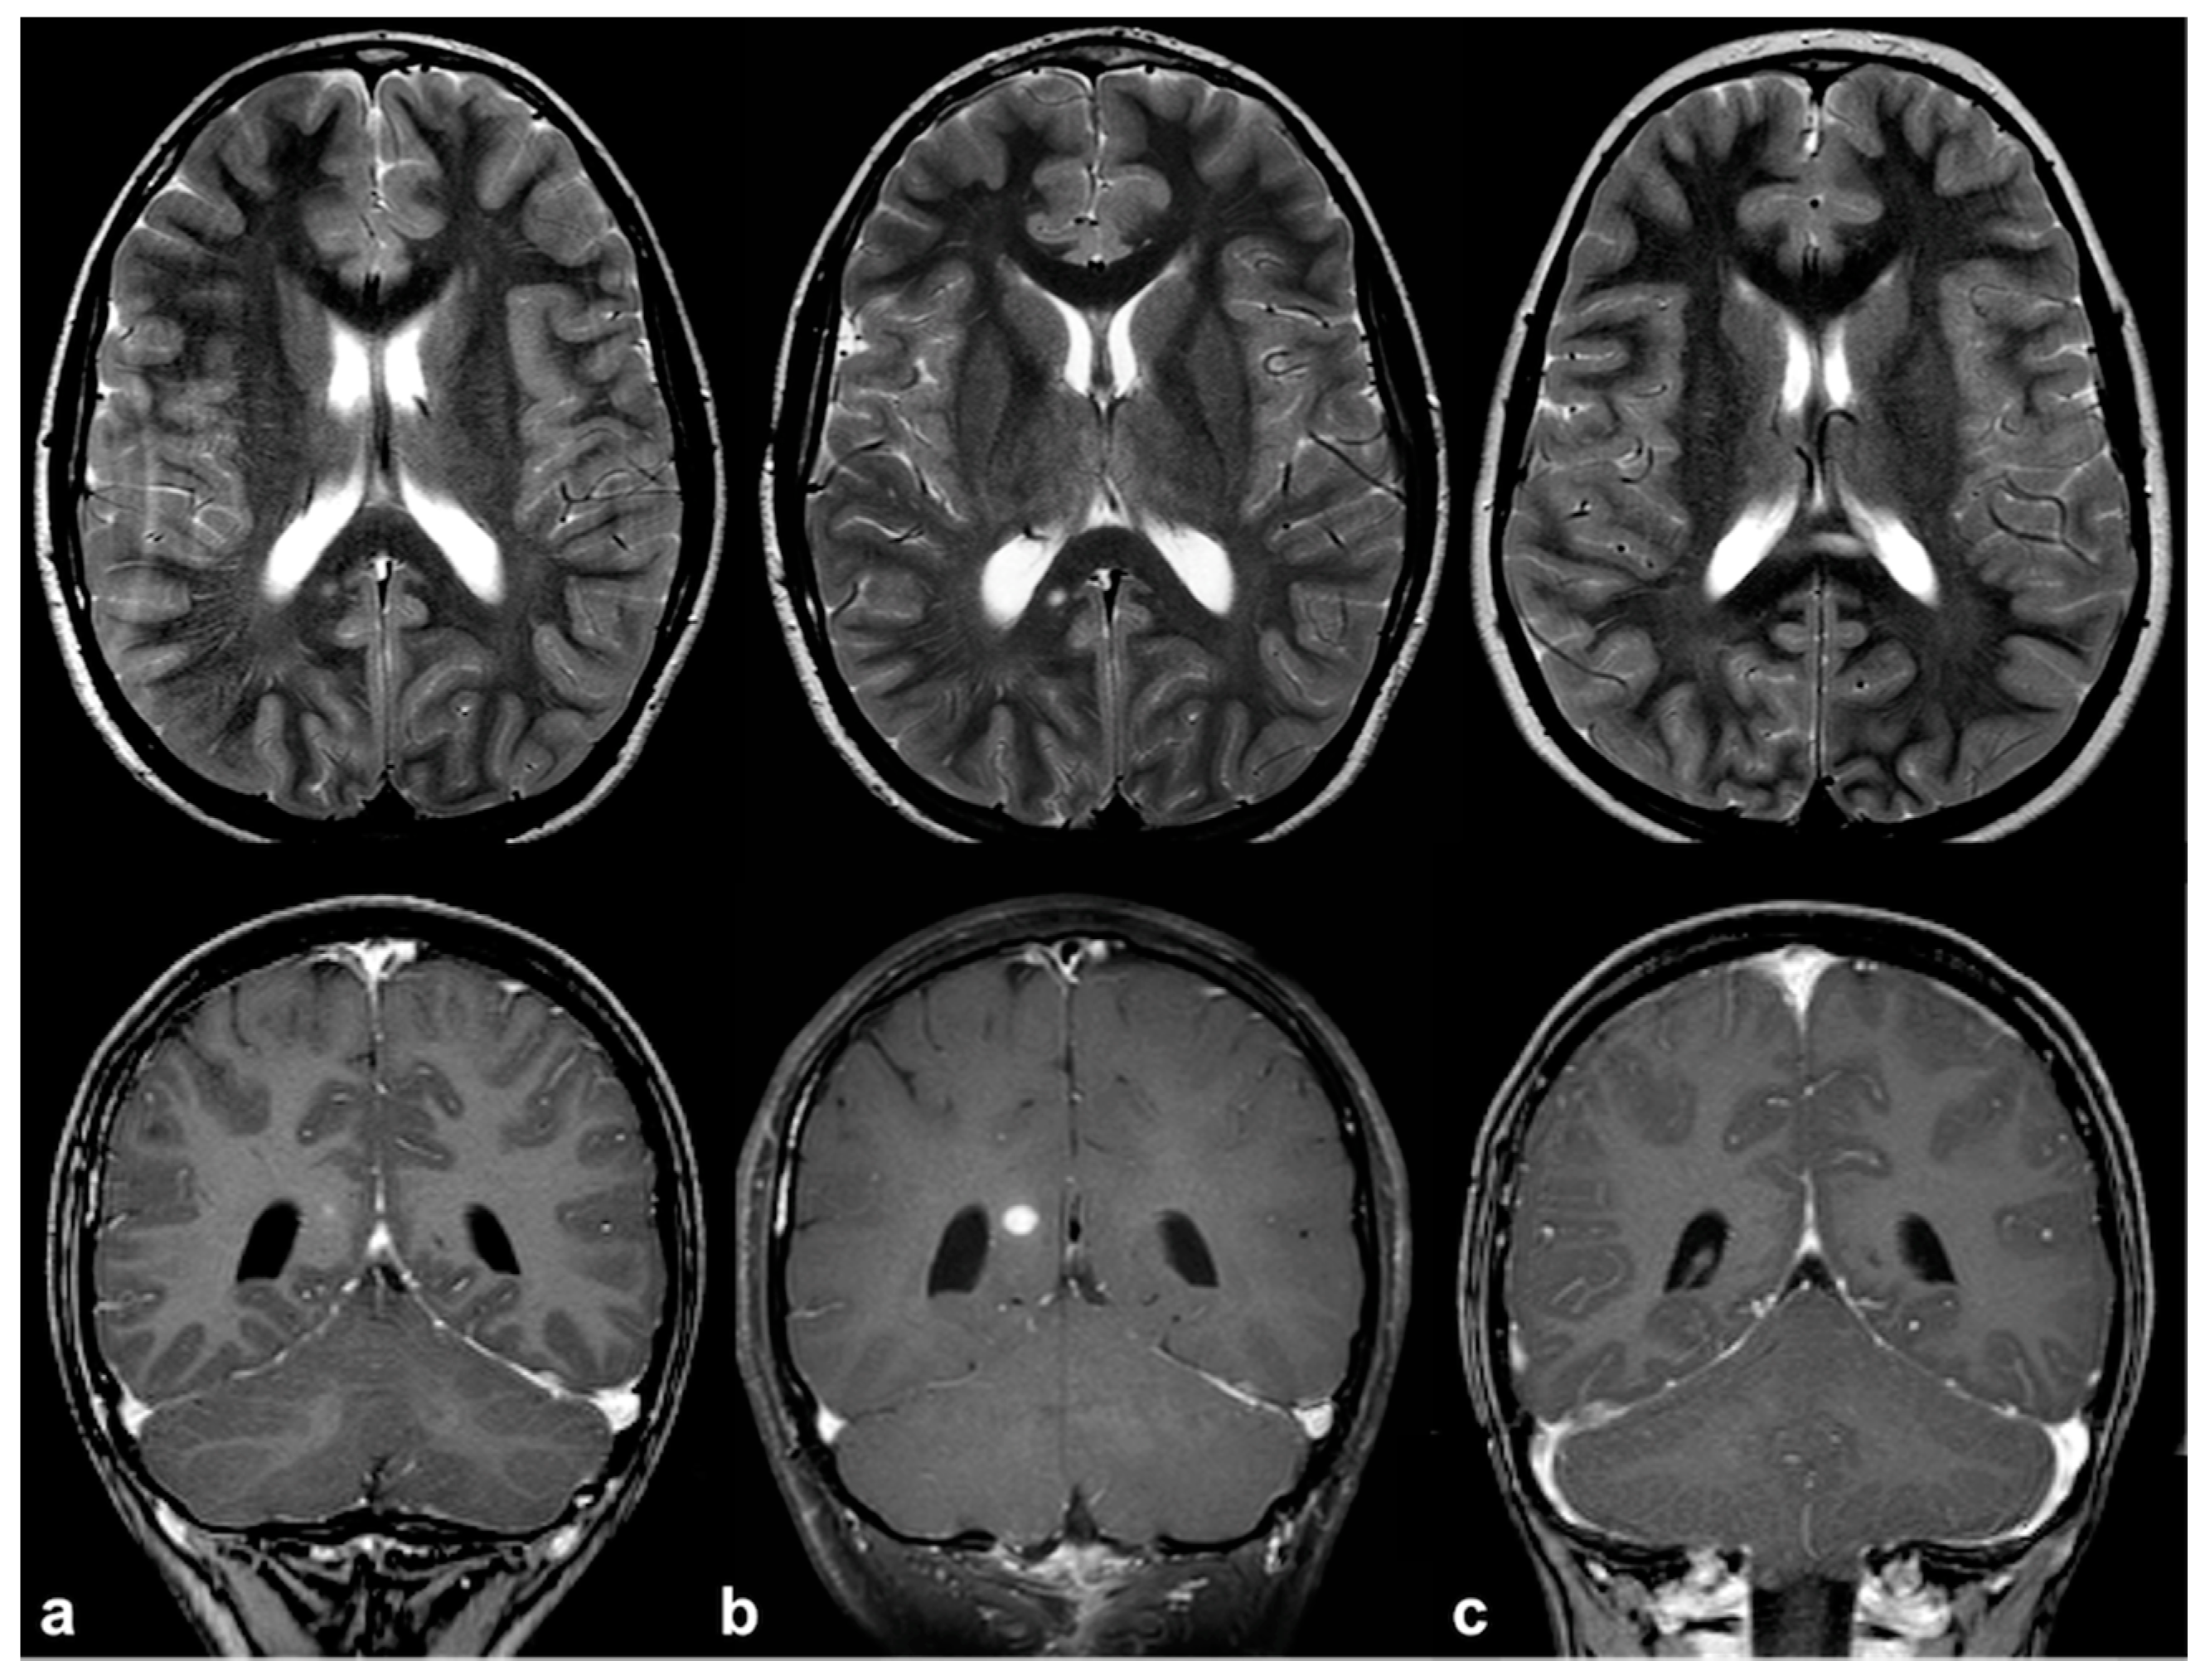

2.1. Focal Abnormal Signal Intensities: Neuroradiological Tips and Tricks